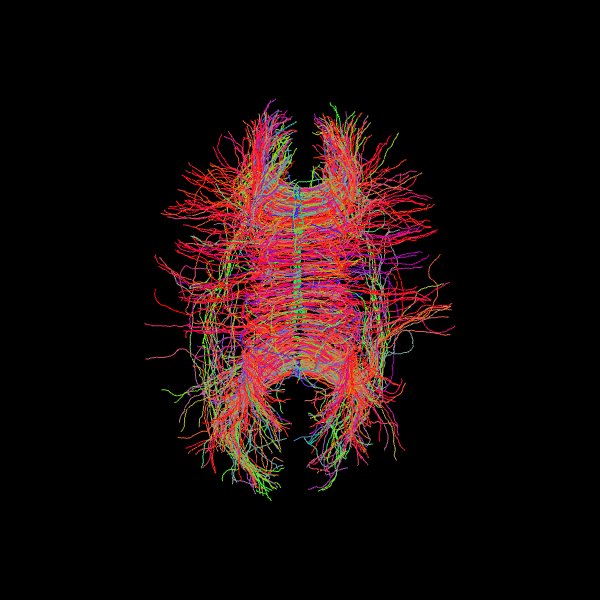

Since we seeded streamlines exclusively from the corpus callosum, all resulting fibers represent interhemispheric connections originating from this region. Let’s visualize them using probabilistic direction getter from SH (peaks_from_model):

scene = window.Scene()

scene.add(actor.line(streamlines_prob, colors=colormap.line_colors(streamlines_prob)))

window.record(scene=scene, out_path="tractogram_probabilistic.png", size=(600, 600))

Image('tractogram_probabilistic.png')